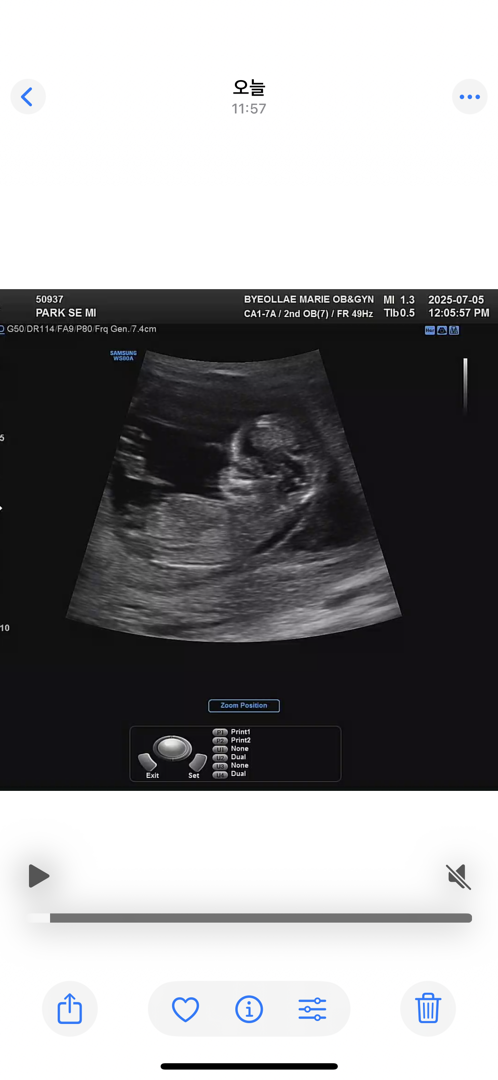

12주 2일 각도법 봐주실 수 있나요 ..🥹

오늘 초음파본거 각도법이 제대로나온게 없어서 그나마 이게 제일 보이는건가 .. ㅠ 싶네용